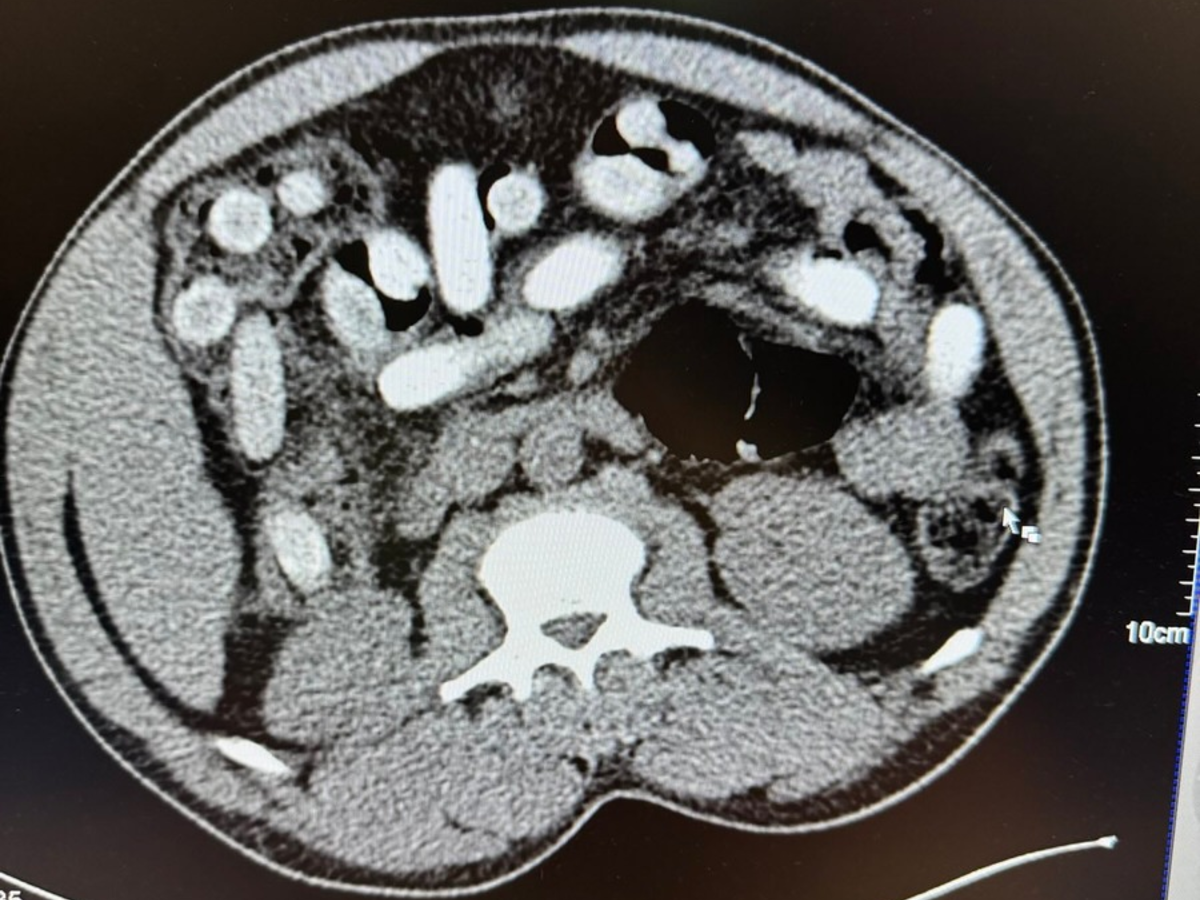

"Die Röntgenaufnahme in einem nahegelegenen Krankenhaus bestätigte letztendlich den Verdacht meiner Kollegen. Der komplette Magen-Darm-Trakt des Mannes war voll mit Drogenpäckchen, sogenannten Bodypacks. In der Größe und Form sind diese mit Datteln vergleichbar. Nach dem Ausscheiden der Drogen war klar, der Mann hatte 111 dieser mit Kokain gefüllten Bodypacks geschluckt. Rund 1,3 Kilogramm Kokain versteckt im Körper ist für uns ein neuer trauriger Rekord. Das Risiko beim Körperschmuggel ist enorm. Wenn nur ein Päckchen im Körper aufgeht, ist das Leben des Mannes nicht mehr zu retten, selbst wenn ein Arzt direkt danebensteht", so Jens Ahland, Pressesprecher des Hauptzollamts Köln.